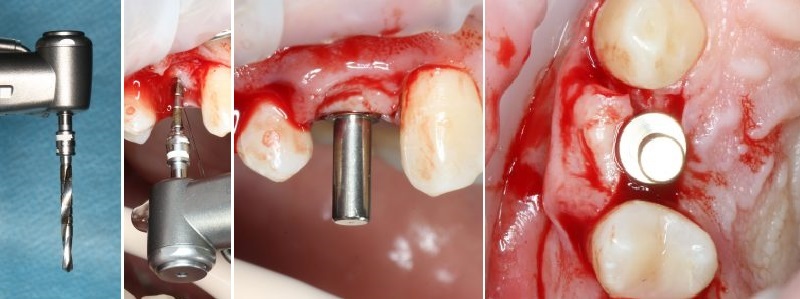

Имплантация начинается с разметки. Проводится это при помощи шаровидного бора

Далее, с помощью пилотной фрезы диаметром 2 мм задаётся ось лунки будущего имплантата, которую контролируем при помощи пинов*

*Штуковина для контроля положения имплантата

Далее, коль ось лунки задана правильно, нам остаётся лишь довести лунку до нужного диаметра. Для этого используются основные рабочие фрезы. Первая из них — диаметром 3.0 мм:

После чего — контроль положения с помощью входящих в набор аналогов имплантатов

На очереди следующая фреза, диаметром 3.4 мм:

И теперь на очереди самый ответственный этап — финишная фреза для нашего имплантата диаметром 3.8 мм. Теперь мы понижаем обороты на физиодиспенсере до минимума, чтобы избежать перегрева и травмы костной ткани, после чего очень-очень аккуратно проходим лунку:

Еще раз проверяем все с помощью аналогов имплантата. Как говорится, семь раз отмерь, один воткни:

Мы довели лунку до глубины 11 мм и диаметра в 3.8 мм. Но на этом подготовка лунки не заканчивается.

А всё потому, что костная ткань — упругая среда, и чтобы снять напряжение с кортикальной пластинки (и предотвратить периимплантит) мы используем специальную кортикальную фрезу:

При работе с очень плотной костной тканью мы дополнительно используем специальный метчик:

Теперь можно приступать к установке имплантата.

Имплантат нужного размера (3.8х11 мм) фиксируется на гексагональном ключе, после чего устанавливается в подготовленную лунку:

Еще раз проверяем поломжение имплантата:

Далее мы убираем временный абатмент, который в данном случае выполнял функцию имплантодержателя

Следующий этап - установка формирователя десны

С учётом клинических условий, мы подобрали к установленному мплантату формирователь Slim (без расширений) высотой 3 мм: